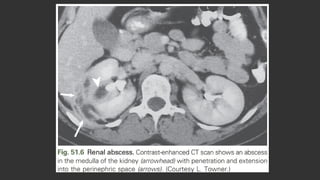

RENAL ABSCESS

 Renal cortical and corticomedullary abscesses and perirenal abscesses occur in 1 to 10

per 10,000 hospital admissions

 CM: fever, chills, back or abdominal pain, and CVA tenderness, but they may have no

urinary symptoms or findings if the abscess does not communicate with the collecting

system, as in cortical abscess

 Bacteremia may be primary (cortical abscess) or secondary (corticomedullary or

perirenal).

 The clinical presentation may be insidious and nonspecific, especially with perirenal

abscess, and the diagnosis may not be made until admission to a hospital or at autopsy

 CT is recommended to establish the diagnosis and location of a renal or perirenal

abscess

 Empiric antibiotic therapy should be broad and cover S. aureus and other uropathogens

causing complicated UTI and modified once urine culture results are known

 renal cortical abscess (renal carbuncle)

 is usually caused by S. aureus, which reaches the kidney by hematogenous spread.

 Treatment  antibiotics, and drainage is not required unless the patient is slow to

respond.

 renal corticomedullary abscess

 usually results from ascending UTI in association with an underlying urinary tract

abnormality, such as obstructive uropathy or VUR

 caused by common uropathogenic species such as E. coli

 may extend deep into the renal parenchyma, perforate the renal capsule, and form a

perirenal abscess.

 Treatment with antimicrobial agents without drainage may be effective if the abscess is

small and if the underlying urinary tract abnormality can be corrected

 Aspiration of the abscess may be necessary in some patients, and nephrectomy may

occasionally be required in patients with diffuse renal involvement or with severe sepsis.

 Perirenal abscesses

 usually occur in the setting of obstruction or other complicating factors (see

Box 51.1)

 result from ruptured intrarenal abscesses, hematogenous spread, or spread

from a contiguous infection.

 Causative uropathogens are those usually found in complicated UTIs

including S. aureus and enterococci; polymicrobial infections are common.

 Anaerobes or Mycobacterium tuberculosis may be causative

 A previously high mortality rate has been lowered with earlier diagnosis and

therapy.

 In contrast to the other types of renal abscesses, drainage of pus is the

cornerstone of therapy and nephrectomy may be indicated.